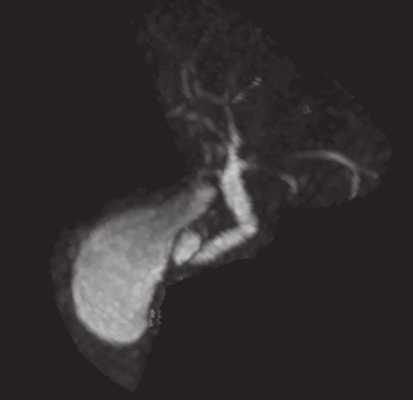

С учетом данных УЗИ проведены МРХПГ и магнитно-резонансная томография органов брюшной полости и забрюшинного пространства. На серии полученных МР-томограмм (на фоне артефактов от движения): печень в размерах не увеличена. Очаговых изменений в паренхиме печени достоверно не выявлено (исследование проводилось без внутривенного контрастного усиления). Желчный пузырь вертикально расположен, размерами 62 х 28 мм, вдоль медиальной стенки пузыря, ближе к шейке, визуализируется небольшое округлой формы жидкостное образование с тонкими стенками размерами 11 х 8 х 12 мм, МР-сигнал от образования идентичен МР-сигналу от содержимого пузыря, при МРХПГ отмечается тонкая шейка между пузырем и образованием диаметром до 1,7 мм; МР-сигнал от содержимого желчного пузыря не изменен, в просвете конкрементов не выявлено (рис. 6).

Рис. 6. МР-холангиопанкреатограмма органов брюшной полости и забрюшинного пространства.

Общий желчный проток несколько расширен до 7 мм, с четкими контурами; пузырный проток хорошо визуализируется диаметром до 3 мм, извит. Общий печеночный проток не расширен (6 мм), область бифуркации хорошо выражена, без особенностей. Долевые протоки не расширены, сегментарные протоки прослеживаются.

Заключение: МР-признаки дивертикула желчного пузыря. Вертикально расположенный желчный пузырь.